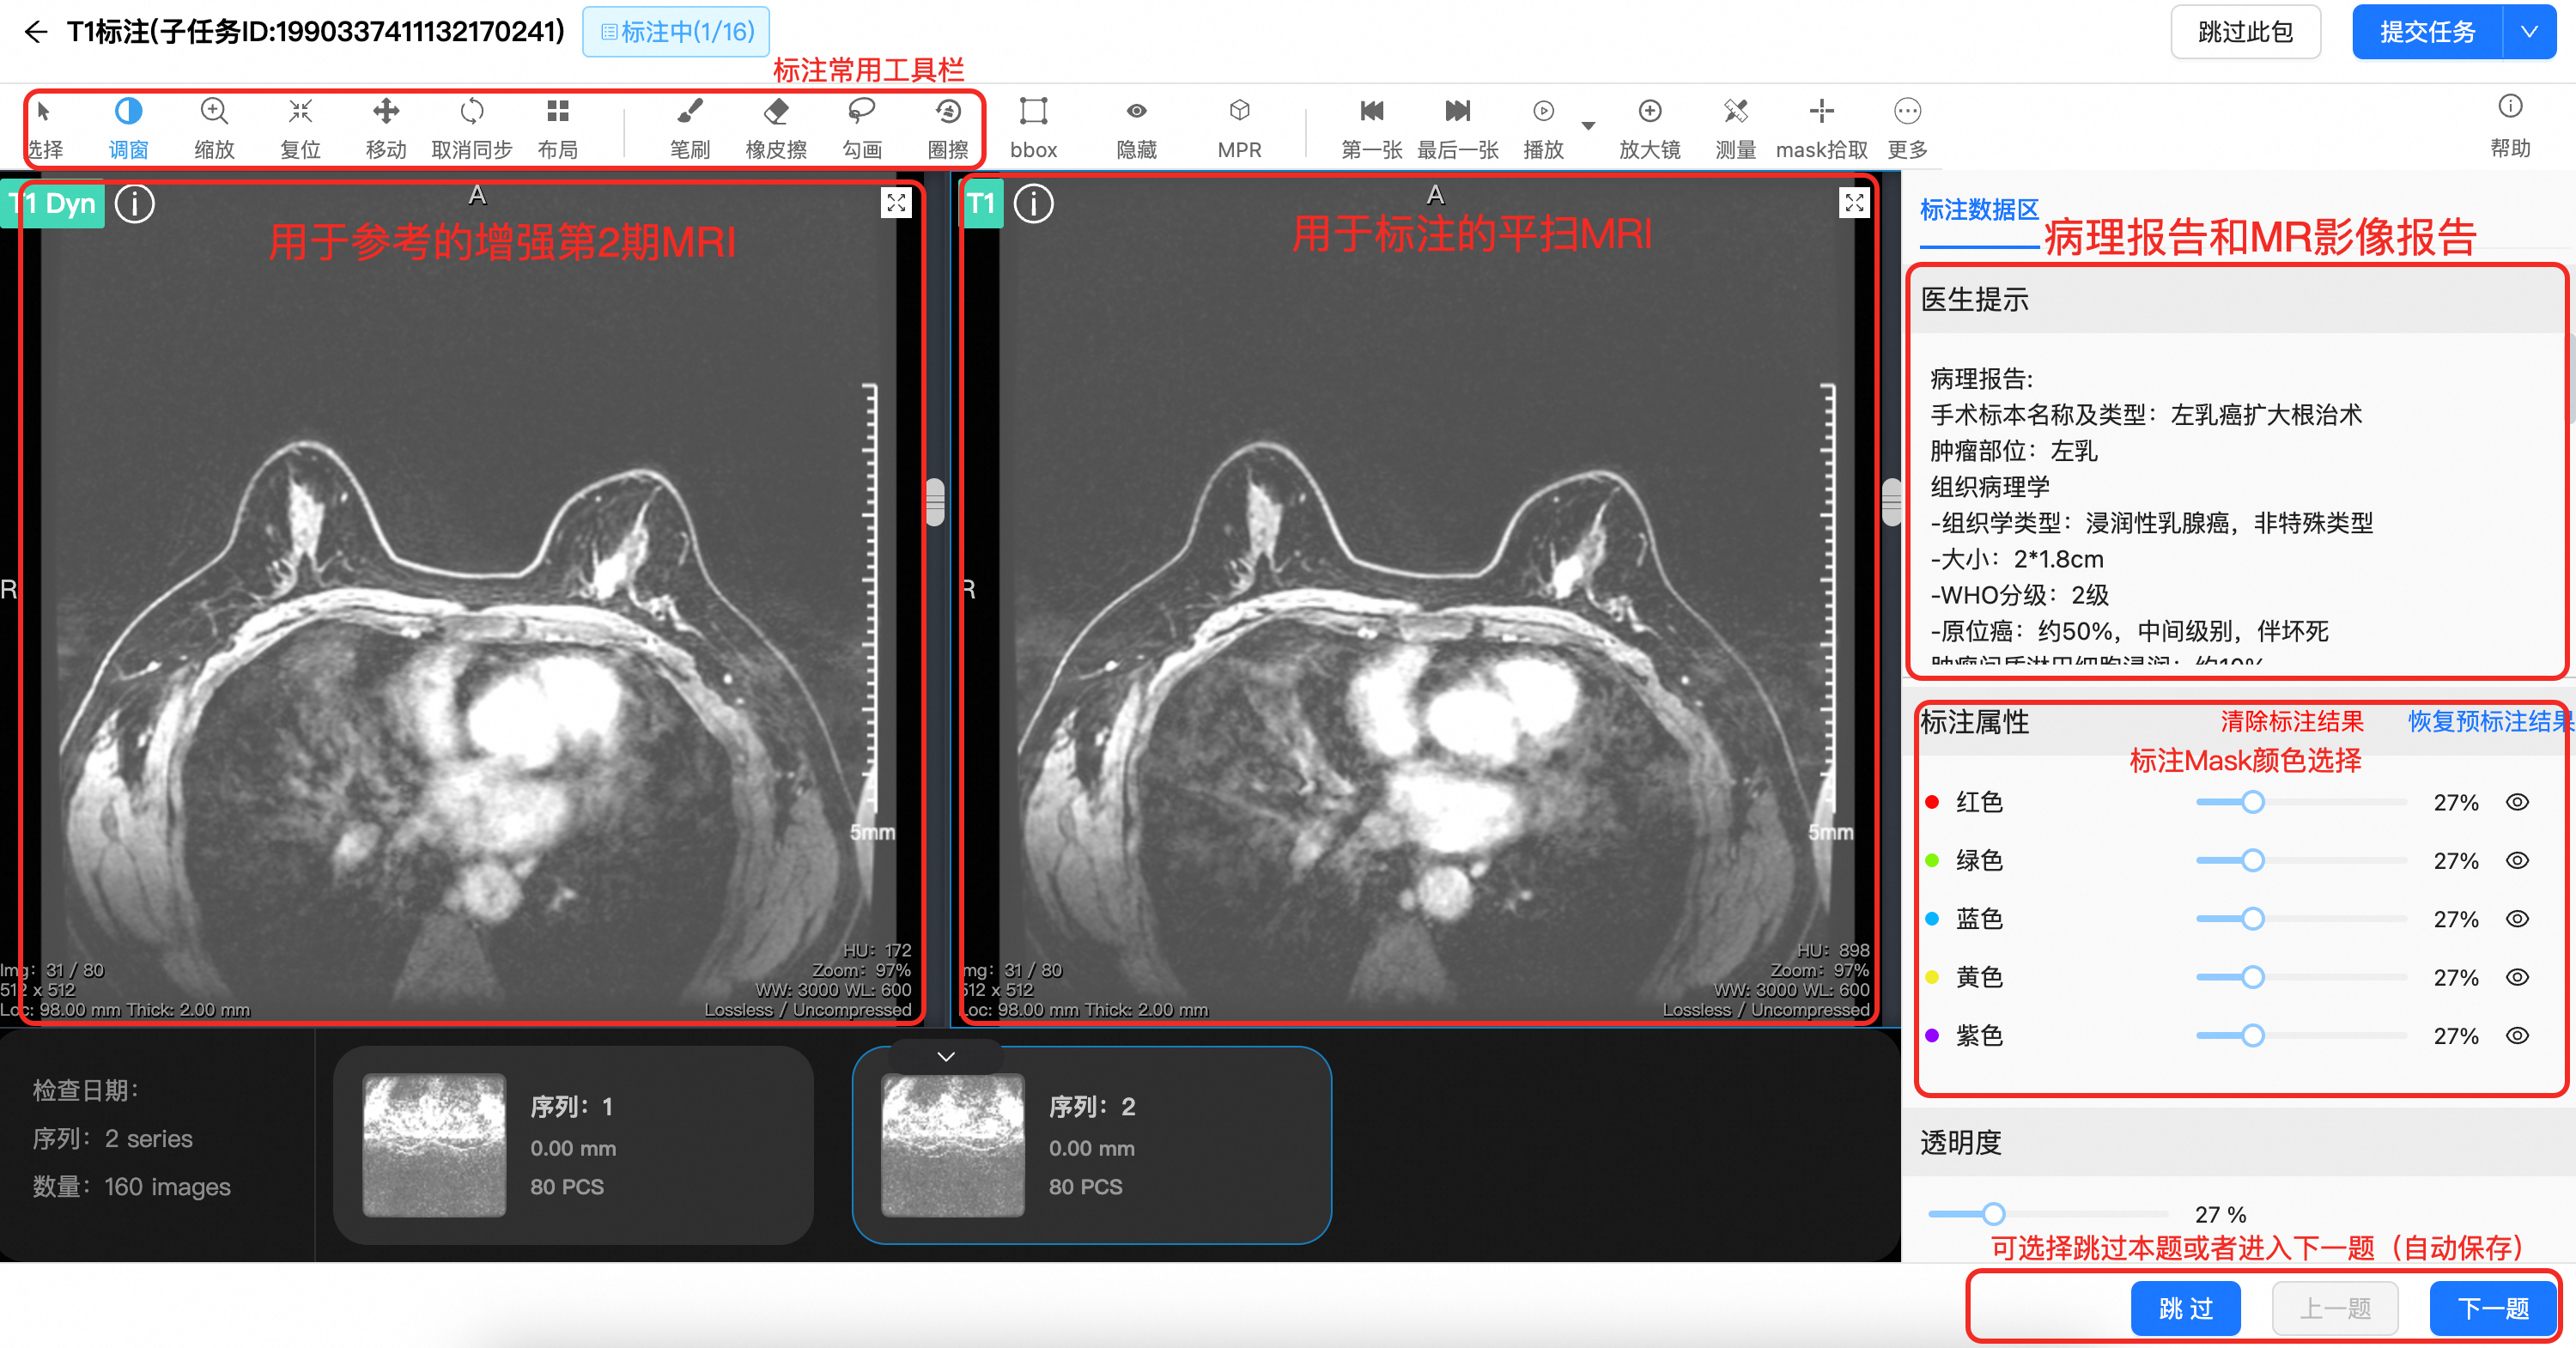

长沙朗慧信息科技有限公司是一家专注于数据标注服务的创新型企业,秉持 “数据驱动,智能创新” 理念,依托人工智能技术和大数据分析,提供高质量、准确、高效的数据标注解决方案。其服务聚焦医疗数据领域,涵盖医学影像、医疗文本及多模态数据融合标注等,通过智能辅助标注、多轮交叉校验等方式保障质量与效率,旨在以数据标注为切入点,助力释放医疗数据价值,推动医疗健康行业智能化发展,用科技改变医疗数据的未来。